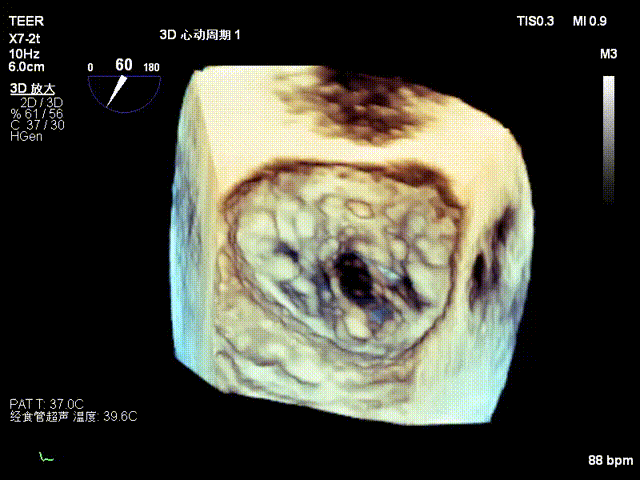

3D

经食道超声检查提示:二尖瓣瓣叶增厚冗长2区后瓣脱垂呈连枷样改变,考虑Barlow’s综合征。评估解剖结构:前叶长度:3.3cm,后叶长度:2.8cm,脱垂宽度:26mm,脱垂高度:19mm,瓣口面积:7.5cm²。

1.P2脱垂腱索断裂连枷样改变,瓣叶整体脱向左房侧,脱垂高度近2.0cm,瓣叶捕获难度极大。

2. Barlow’s综合征,瓣叶增厚冗长且质量欠佳,夹子稳定性差,且需谨防SLDA风险。